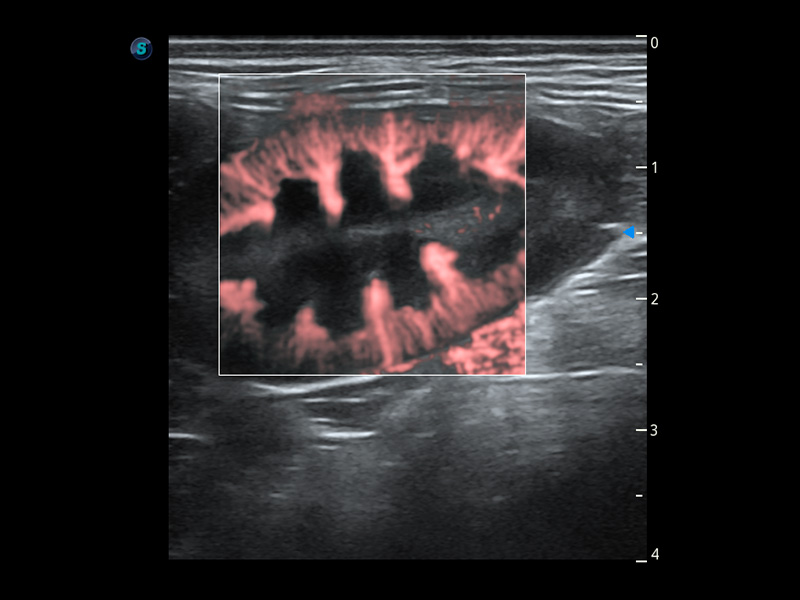

4T血流成像 微察秋毫

融合不同血流成像技术的优势,即可以提升血流成束性,同时可提高血流的视觉敏感性。

PDI 能量多普勒血流

提供高灵敏度和空间分辦率的血流图像,获得更加真实和丰富的诊断信息。

SR Flow 高分辨率血流成像

能够清晰显示细小、低速血流图像,获取传统彩色多普勒技术难以得到的细节和信息。

Micro F 显微血流成像

通过创新的Matrix E自适应滤波器和超长时间域算法,极大提升超低速微细血流的检出能力,同时更精准地滤除软组织和噪声信号,为兽用医生提供以往无法通过常规血流获得的疾病诊断信息。

Bright Flow 立体血流成像

在传统二维血流成像的基础上,呈现血流的立体感,具有动感的生命力之美。精确区分不同血管的空间关系,提高了血流的视觉敏感性。

(猫)髂动脉血流频谱

(犬)肾脏血流